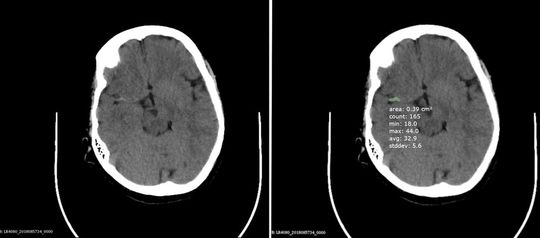

Abb. 1: Schädel-CT, links originale Schicht, rechts dieselbe Schicht, auf der der KI-Assistent den Thrombus erkannt und richtig umrandet hat. Diese Segmentierung erfolgt automatisch über mehrere aneinander grenzende Schichten, und zu jeder werden Kenngrößen zu Größe und Grauwertverteilung ermittelt(© UKSH und mbits, Heidelberg)

Abb. 1: Schädel-CT, links originale Schicht, rechts dieselbe Schicht, auf der der KI-Assistent den Thrombus erkannt und richtig umrandet hat. Diese Segmentierung erfolgt automatisch über mehrere aneinander grenzende Schichten, und zu jeder werden Kenngrößen zu Größe und Grauwertverteilung ermittelt

Der KI-Notfalldiagnostik-Assistent wird zunächst in drei Anwendungsbereichen trainiert: Schlaganfälle, Knochenverletzungen und Brustkorbuntersuchungen. Auf allen drei Gebieten geht es hauptsächlich darum, Probleme frühzeitig zu erkennen, die einer möglichst schnellen Behandlung bedürfen, zum Beispiel die richtige Platzierung von Kathetern, die der KI-Assistent anhand von Röntgenbildern überprüfen kann. Wenn in der Notaufnahme der Verdacht auf Schlaganfall besteht, soll das System anhand des Bildes automatisch erkennen, ob ein verschlossenes Blutgefäß oder eine Hirnblutung die Ursache ist – die dann jeweils nötige Therapie ist in den beiden Fällen grundlegend unterschiedlich – und, wenn ein Thrombus vorliegt, diesen markieren (Abb. 1). Bei der Untersuchung von Knochenbrüchen nach Unfällen kann die Bildanalyse erkennen, ob überhaupt ein akuter neuer Bruch vorliegt und auch, ob der frische Bruch etwa instabil ist (Abb. 2), so dass die Behandlung potenziell mit besonderer Vorsicht durchgeführt werden muss. Ärztinnen und Ärzte erhalten so eine schnelle fundierte Entscheidungsgrundlage für Notfallbehandlungen. Potenzielle Anwendungsgebiete darüber hinaus sind vielfältig. Vor allem kleinere Kliniken, denen es an entsprechender spezialisierter radiologischer Expertise fehlt, können von der KI-Anwendung profitieren. Eventuell kann sie sogar zu Trainingszwecken eingesetzt werden – nachdem die KI auf der Grundlage von Trainingsdaten gelernt hat, entsprechende Auffälligkeiten zu erkennen und von Experten freigegeben wurde, könnte die KI schließlich bei der Schulung von externem medizinischem Personal unterstützen.